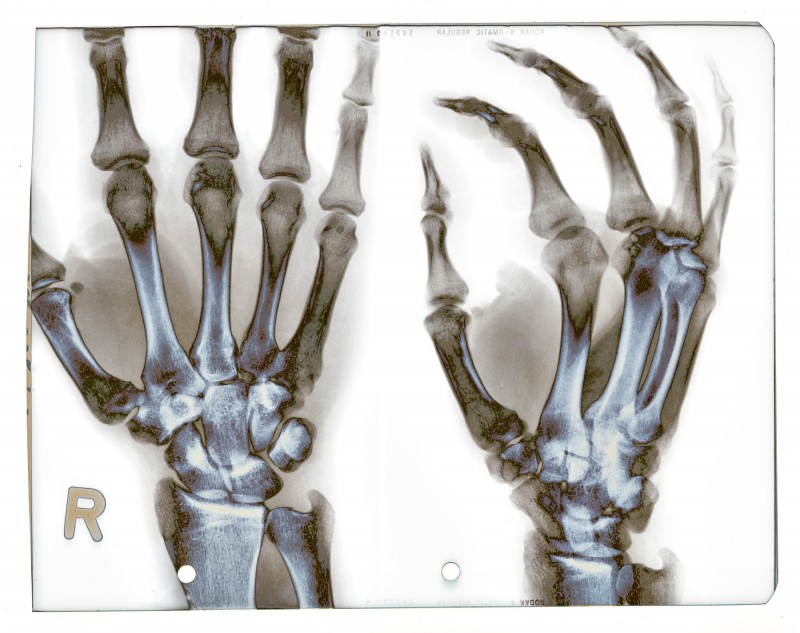

x-rays